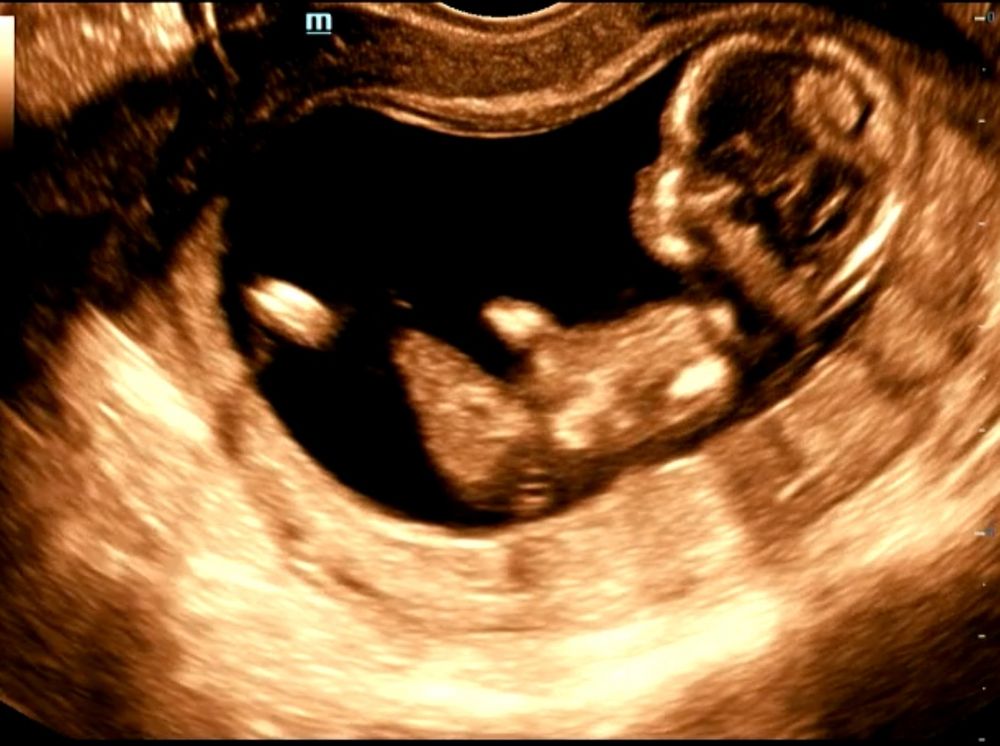

Как думаете кто по УЗИ? Первый скрининг.

Женя, вот как раз и пыталась разглядеть половой бугорок))) но не уверена, что это именно оно, а не часть ноги так засветилась или пуповина, срок здесь 12 и 1

Маленькая , похоже на половой бугорок, но Вы же понимаете что из меня "эксперт" может быть ещё тот)) Я специально просила мне дать снимок с бугорком поэтому знаю что у меня это он